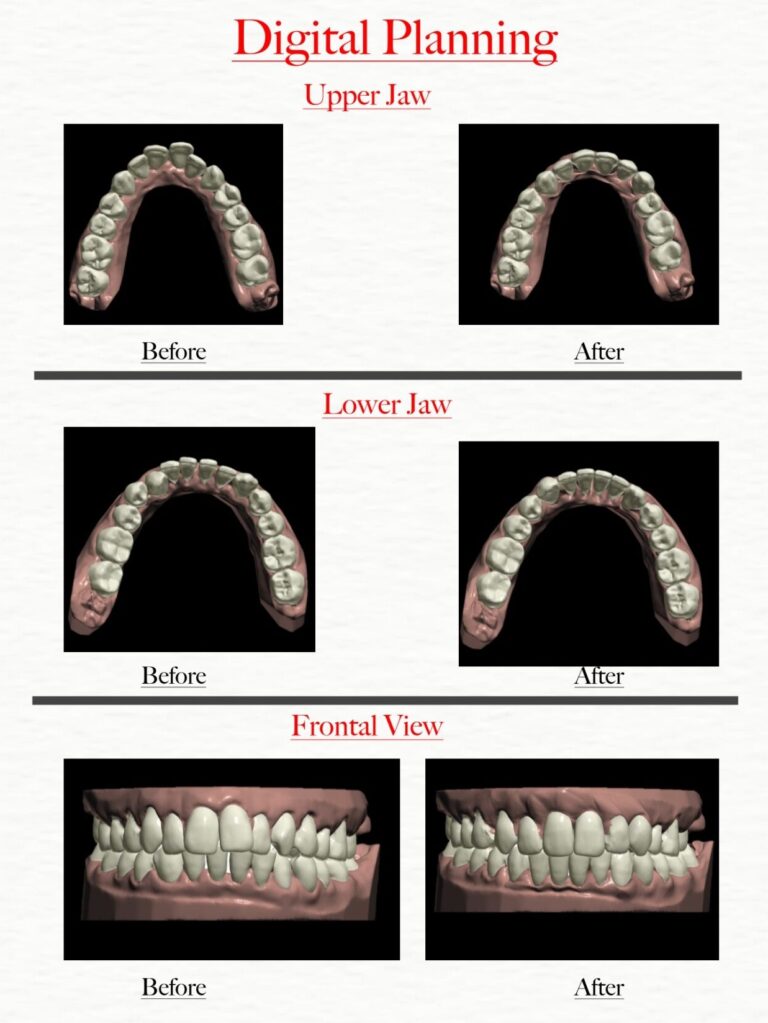

Second Consultation: The orthodontist will show you a digital planning which includes your overall planning, future predicted teeth alignment and timeline

Predictability: The 3D imaging and digital treatment planning process provides a clear picture of the expected results and timeline